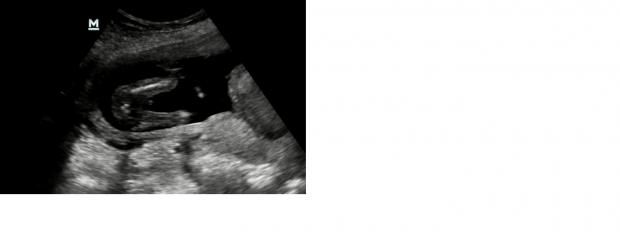

Hi everyone

I share four pictures and a video. The video is filmed from the underside of the baby.

Please, does anyone know, I really have no idea?